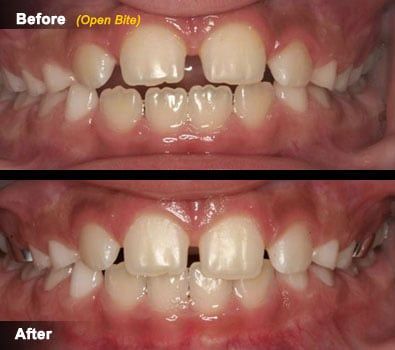

Open Bite and Cross Bite

These are two common problems in children that have their origin in discrepancies between the size of the jaws (top and bottom), or discrepancies between the size of the teeth and the amount of space available.

- A posterior cross bite can appear at an early age, and depending on its cause (malpositioned teeth or misaligned jaws) treatment may be warranted early. It can involve one or both sides of the molar area and in some cases in can cause a "shift" of the bite. Many appliances are available for treating this condition and your dentist will discuss in detail the risks and benefits of treating a posterior cross bite.

- Anterior open bites refer to a condition in which the top and bottom front teeth are not in contact (they do not touch each other when the patient bites). The origins of open bites can be traced to habits that patients have or had in the past, and occasionally to discrepancies between the sizes of the jaws. Since most open bites in children are associated to an existing habit, treatment usually addresses the habit itself and is most effective when done at an early age. Many appliances are available for treating this condition and your dentist will discuss in detail the risks and benefits of treating an open bite in children.